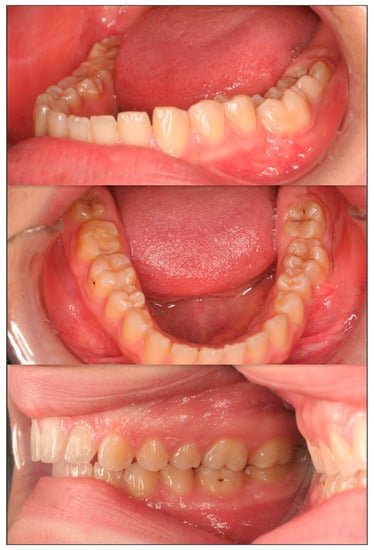

2. Case Presentation